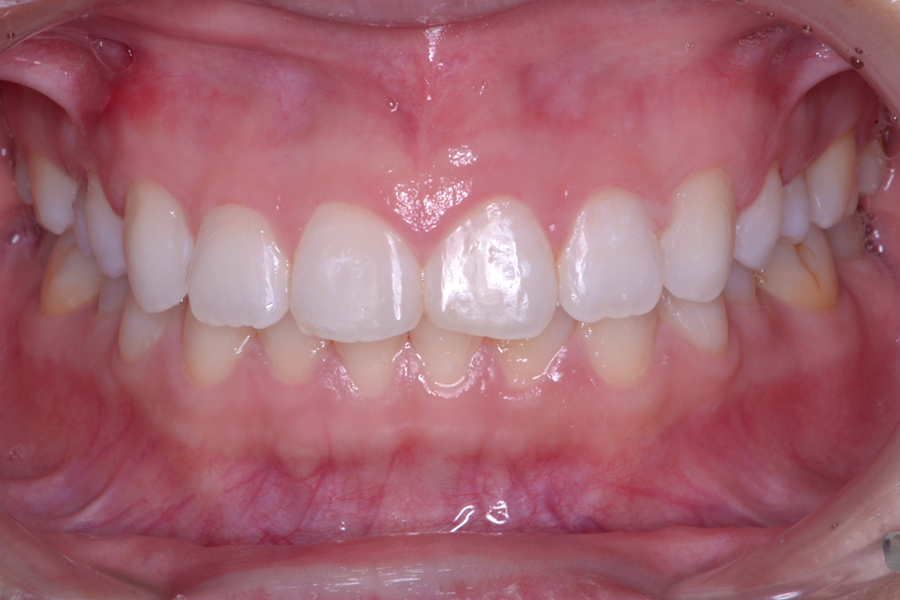

• 治療前

治療後

主訴 前歯のガタツキを治して前歯でものを咬み切れるようになりたい

治療内容 ハーフリンガル矯正(上顎裏側・下顎表側矯正)

リスク 後戻り